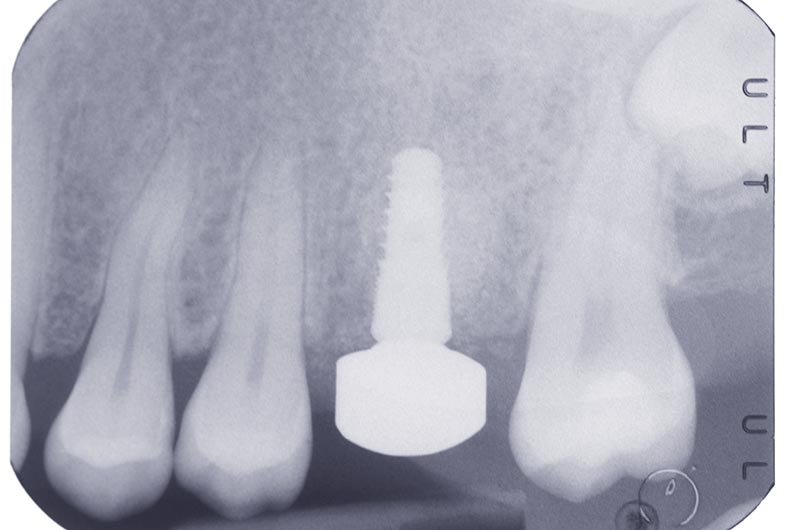

Après trois mois, un implant Naturall+, de diamètre 4 x 10 mm, est posé en remplacement de la 26. La stabilité primaire mesurée au moment de la pose de l’implant est supérieure à 35 N.cm.

Après la pose de l’implant, la stabilité primaire autorise la mise en place d’un pilier de cicatrisation. L’implant Naturall+ permet de choisir dans une sélection de 9 formes anatomiques de pilier de cicatrisation (3 profils et 3 hauteurs) (fig. 2 et 3).

Pour fixer le pilier de cicatrisation, une interface Esthetibase est posée sur l’implant. Il existe de nombreuses interfaces permettant de s’adapter à la plupart des marques d’implants sur le marché. Le pilier iphysio® C1 choisi est clipsé sur l’interface (fig. 4).